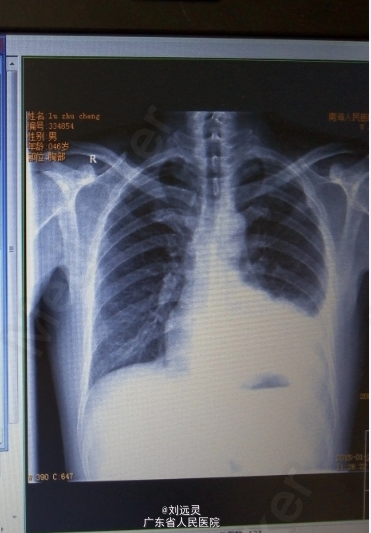

男,46岁。 因"低热、咳嗽10余天"入院。 患者于10余天前在无明显诱因下出现发热,最高体温37.5℃,无畏寒寒战,以夜间出现,伴咳嗽,程度轻,咳少许白色粘痰,痰中无带血丝,无铁锈色痰,无胸痛,曾在当地医院治疗,予抗病毒,抗感染等治疗,(具体不详),但症状缓解不明显,行胸片示:左肺炎并左侧胸腔积液。今为进一步治疗,拟"左下肺炎"收住本科。

体查:T:37℃ P:105次/分 R:20次/分 BP:107/73mmHg,神清,急性面容,全身皮肤、粘膜无出血点及瘀斑,无黄染,全身浅表淋巴结不大,结膜无充血水肿,唇无发绀,咽充血,双侧扁桃体不大,未见脓点,胸廓无畸形,未见明显三凹征,肋间隙增宽,触觉语颤对称,无胸膜摩擦感及皮下捻发感,右肺叩诊呈清音,左下肺叩诊呈浊音,右肺呼吸音粗,左肺呼吸音低,双肺未闻及干湿啰音,未闻及胸膜摩擦音。心、腹正常。辅助检查:外院胸片示:左肺炎并左侧胸腔积液。血常规、凝血功能阴性,HCV-Ab+HIV-Ab+TP-Ab+HBsAg 阴性,ESR 34 ↑ mm/h PCT 0.0900 ↑ ng/ml 大小二便常规、肝肾功能电解质血脂正常,超敏C反应蛋白 hCRP 44.65 ↑ mg/L 。胸水B超定位:左侧胸腔中量积液声像右侧胸腔未见明显液暗区。鳞状上皮细胞>25个/LP;白细胞<10个/LP(标本取材较差,主要来源于上呼吸道),上呼吸道正常菌群 痰涂片:未找到抗酸杆菌。 PPD(+)胸水找细菌:WBC++,未找到细菌及真菌,胸水常规、生化支持结核性胸腔积液。胸部CT平扫:1.左上肺多发片结状密影性质待定,占位病变与炎性病变相鉴别,建议增强扫描进一步检查;2、拟左下肺炎;3、左侧胸腔中等量积液,左下肺外压性肺不张;4、纵隔多发小淋巴结显示。甲功、肿瘤标志物阴性。纤维支气管镜检查:双侧支气管炎,刷检左上叶尖段支气管找肿瘤细胞及抗酸杆菌:未找到抗酸杆菌。液基薄层细胞制片术:(胸水)镜下:见间皮细胞及炎细胞,未查见明显恶性肿瘤细胞。复查肝肾功能电解质血脂:尿酸 UA 653 ↑ μmol/L 白蛋白 ALB 35.2 ↓ g/L 血常规正常。复查胸部CT平扫:1、左上肺多发片结状密影较前变化不大,性质待定,占位病变与炎性病变相鉴别,建议增强扫描进一步检查;2、拟左肺下叶、上叶下舌段肺炎;3、左侧液气胸,肺组织约受压5%,其中气胸为新发,胸腔积液量较前略有减少;4、纵隔多发小淋巴结显示。

诊断:1.结核性胸腔积液 2.左下肺炎 3.左侧气胸。处理:予左克抗感染,行三次胸水常规生化定性结核性后停用,用IRZE四联抗结核+口服激素治疗。